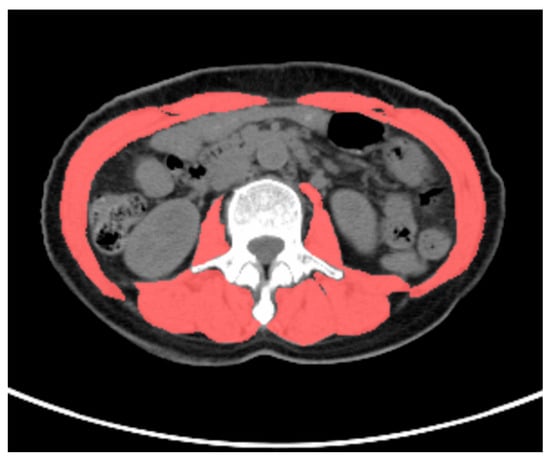

All PET/CT images were delineated by two nuclear medicine physicians, who were blinded to the clinical data. The VAT SUVmean, SAT SUVmean, and skeletal muscle cross-sectional area were obtained using the LIFEx software version 7.4.0. VAT and SAT regions at the L4–L5 vertebral level across three consecutive CT slices were delineated based on CT attenuation values, ranging from −50 Hounsfield units (HU) to −150 HU [13]. These CT-defined VAT and SAT regions were mapped onto the corresponding PET/CT fusion images to acquire the VAT SUVmean and SAT SUVmean, as shown in Figure 1. The total skeletal muscle cross-sectional area at the L3 level (including the psoas major, erector spinae, quadratus lumborum, transversus abdominis, internal oblique, external oblique, and rectus abdominis muscles) was delineated based on the CT attenuation range (−29 HU to 150 HU) on CT images, as shown in Figure 2. The skeletal muscle index (SMI) at L3 was calculated as follows: skeletal muscle cross-sectional area at L3 (cm2)/height squared (m2) [22].

Figure 2. Methodology for measuring skeletal muscle cross-sectional area. A 58-year-old female patient with gastric cancer underwent preoperative 18F-FDG PET/CT examination. The total skeletal muscle cross-sectional area at the L3 vertebral level was delineated based on a CT attenuation range (−29 HU to 150 HU (scarlet color )) on CT images using LIFEx software version 7.4.0. The total skeletal muscle cross-sectional area at the L3 vertebral level in this patient was 91.2 cm2.